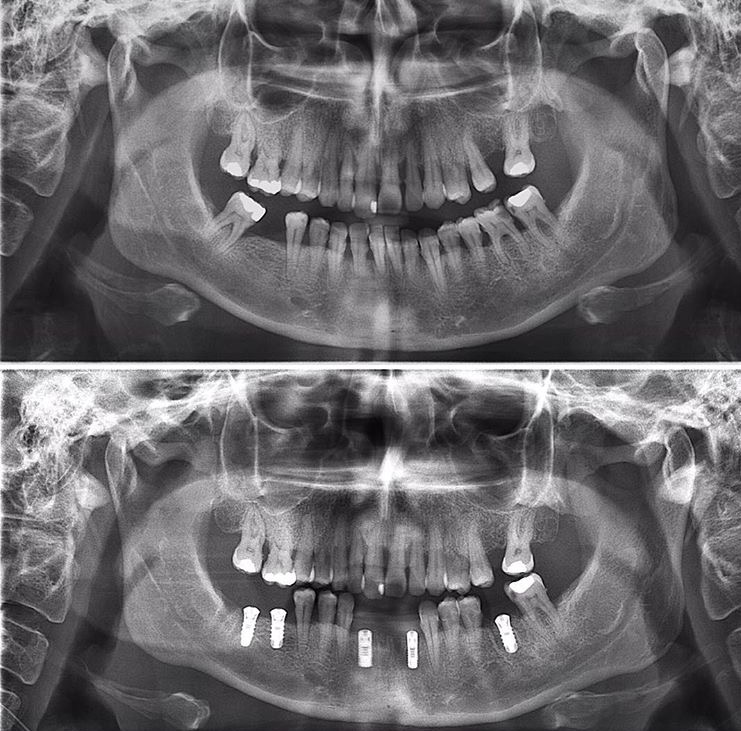

Tansel Hamza

Diş Estetiği ve İmplant (Bölüm 3)